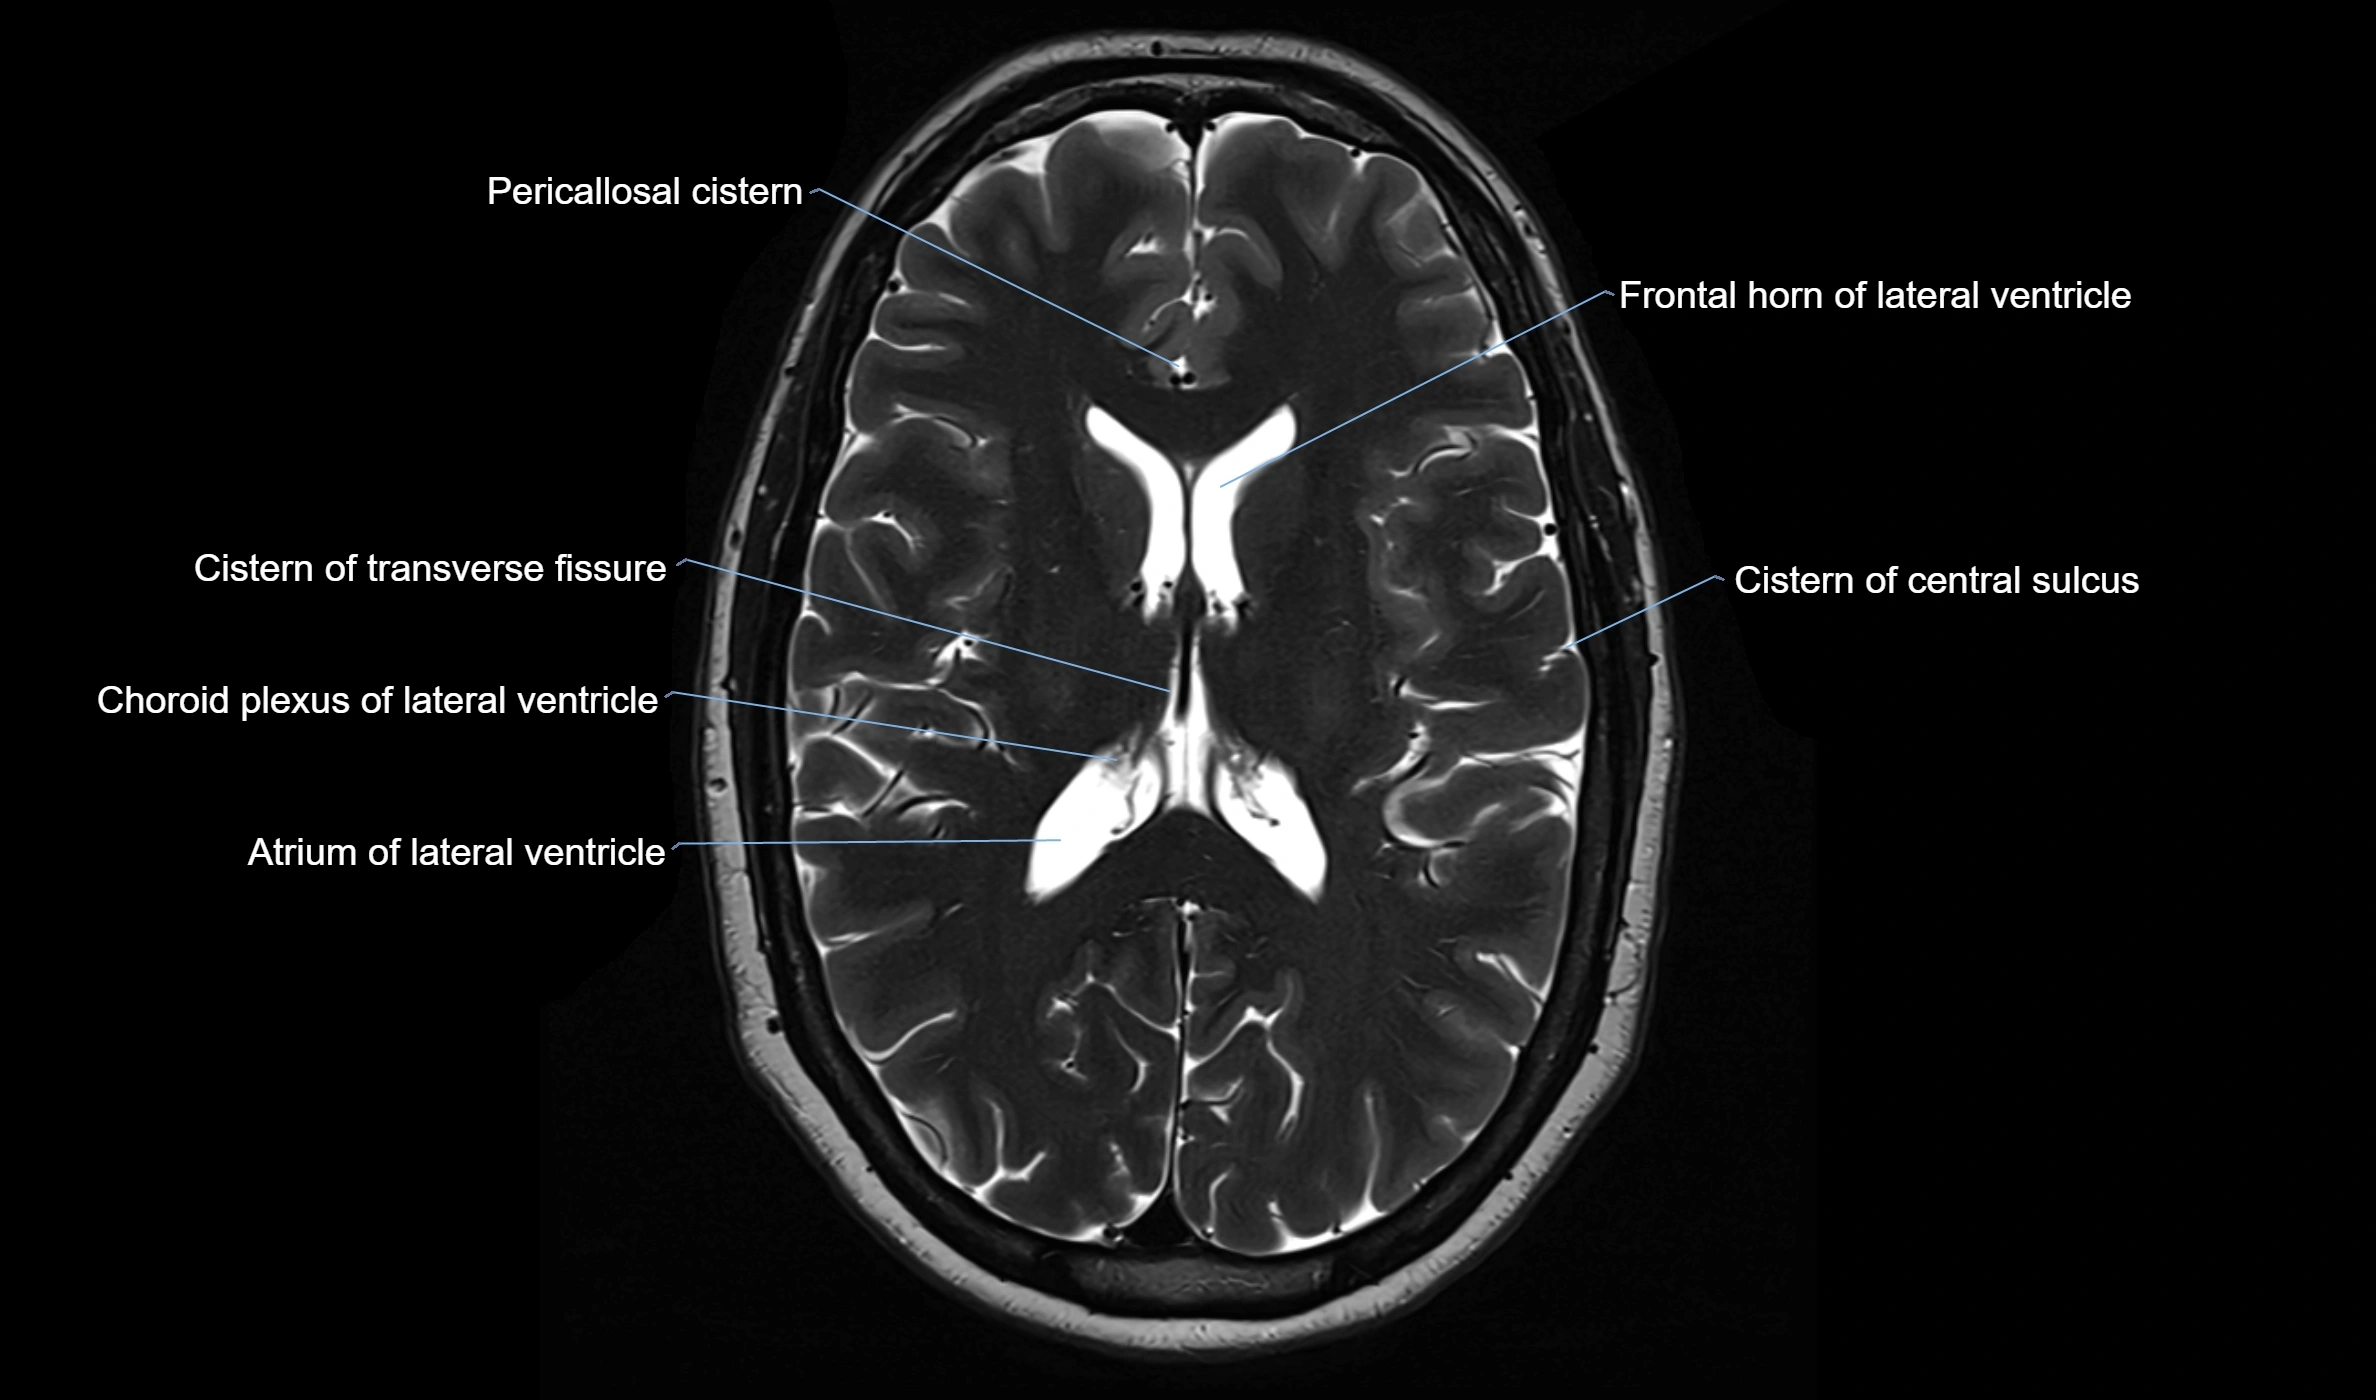

MRI images

image